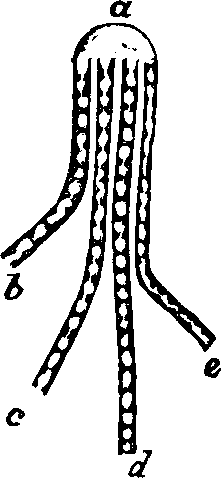

Generation. So long as the vital principle remains in the sperm-cell, it lies dormant. That part of the cell which contains this principle is called the spermatozoön, which consists of a flattened body, having a long appendage tapering to the finest point. If it be remembered that a line is the one-twelfth part of an inch in length, some idea may be formed of the extreme minuteness of the body of a human spermatozoön, when we state that it is from 1/800 to 1/600 part of a line, and the filiform tail 1/50 of a line, in length. This life-atom, which can be discerned only with a powerful magnifying glass, is perfectly transparent, and moves about by executing a vibratile motion with its long appendage. Within this speck of matter are hidden the multifarious forces which, under certain favorable conditions, result in organization. Magnify this infinitesimal atom a thousand times, and no congeries of formative powers is perceived wherewith to work out the wonders of its existence. Yet it contains the principle, which is the contribution on the part of the male toward the generation of a new being.

Fig. 1. A. Human

Spermatozoön magnified about 3,800 diameters. B. Vertical and

lateral views of spermatozoa of man. C, D, E, F. Development of

spermatozoa within the vesicles of evolution. G. Cell of the sponge

resembling a spermatozoön. H. Vesicles of evolution from the

seminal fluid of the dog in the parent cell I. Single vesicles of

different sizes. J. Human spermatozoön forming in its cell.

K. Rupture of the cell and escape of the spermatozoön.